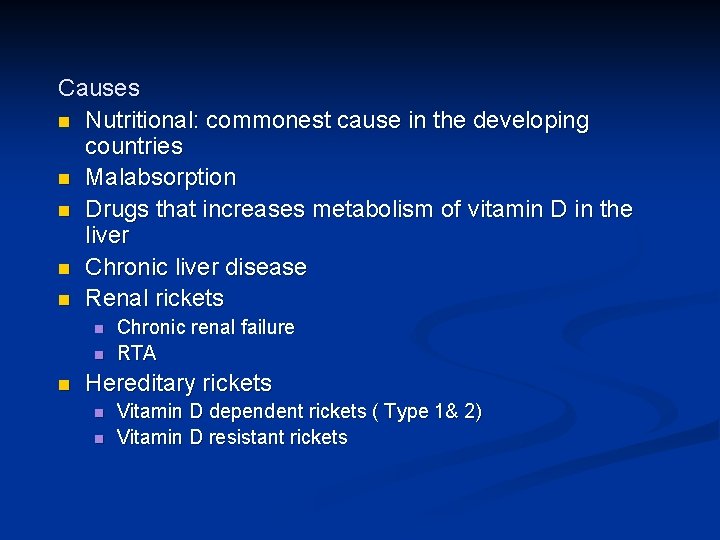

Causes n Nutritional: commonest cause in the developing countries n Malabsorption n Drugs that increases metabolism of vitamin D in the liver n Chronic liver disease n Renal rickets n n n Chronic renal failure RTA Hereditary rickets n n Vitamin D dependent rickets ( Type 1& 2) Vitamin D resistant rickets